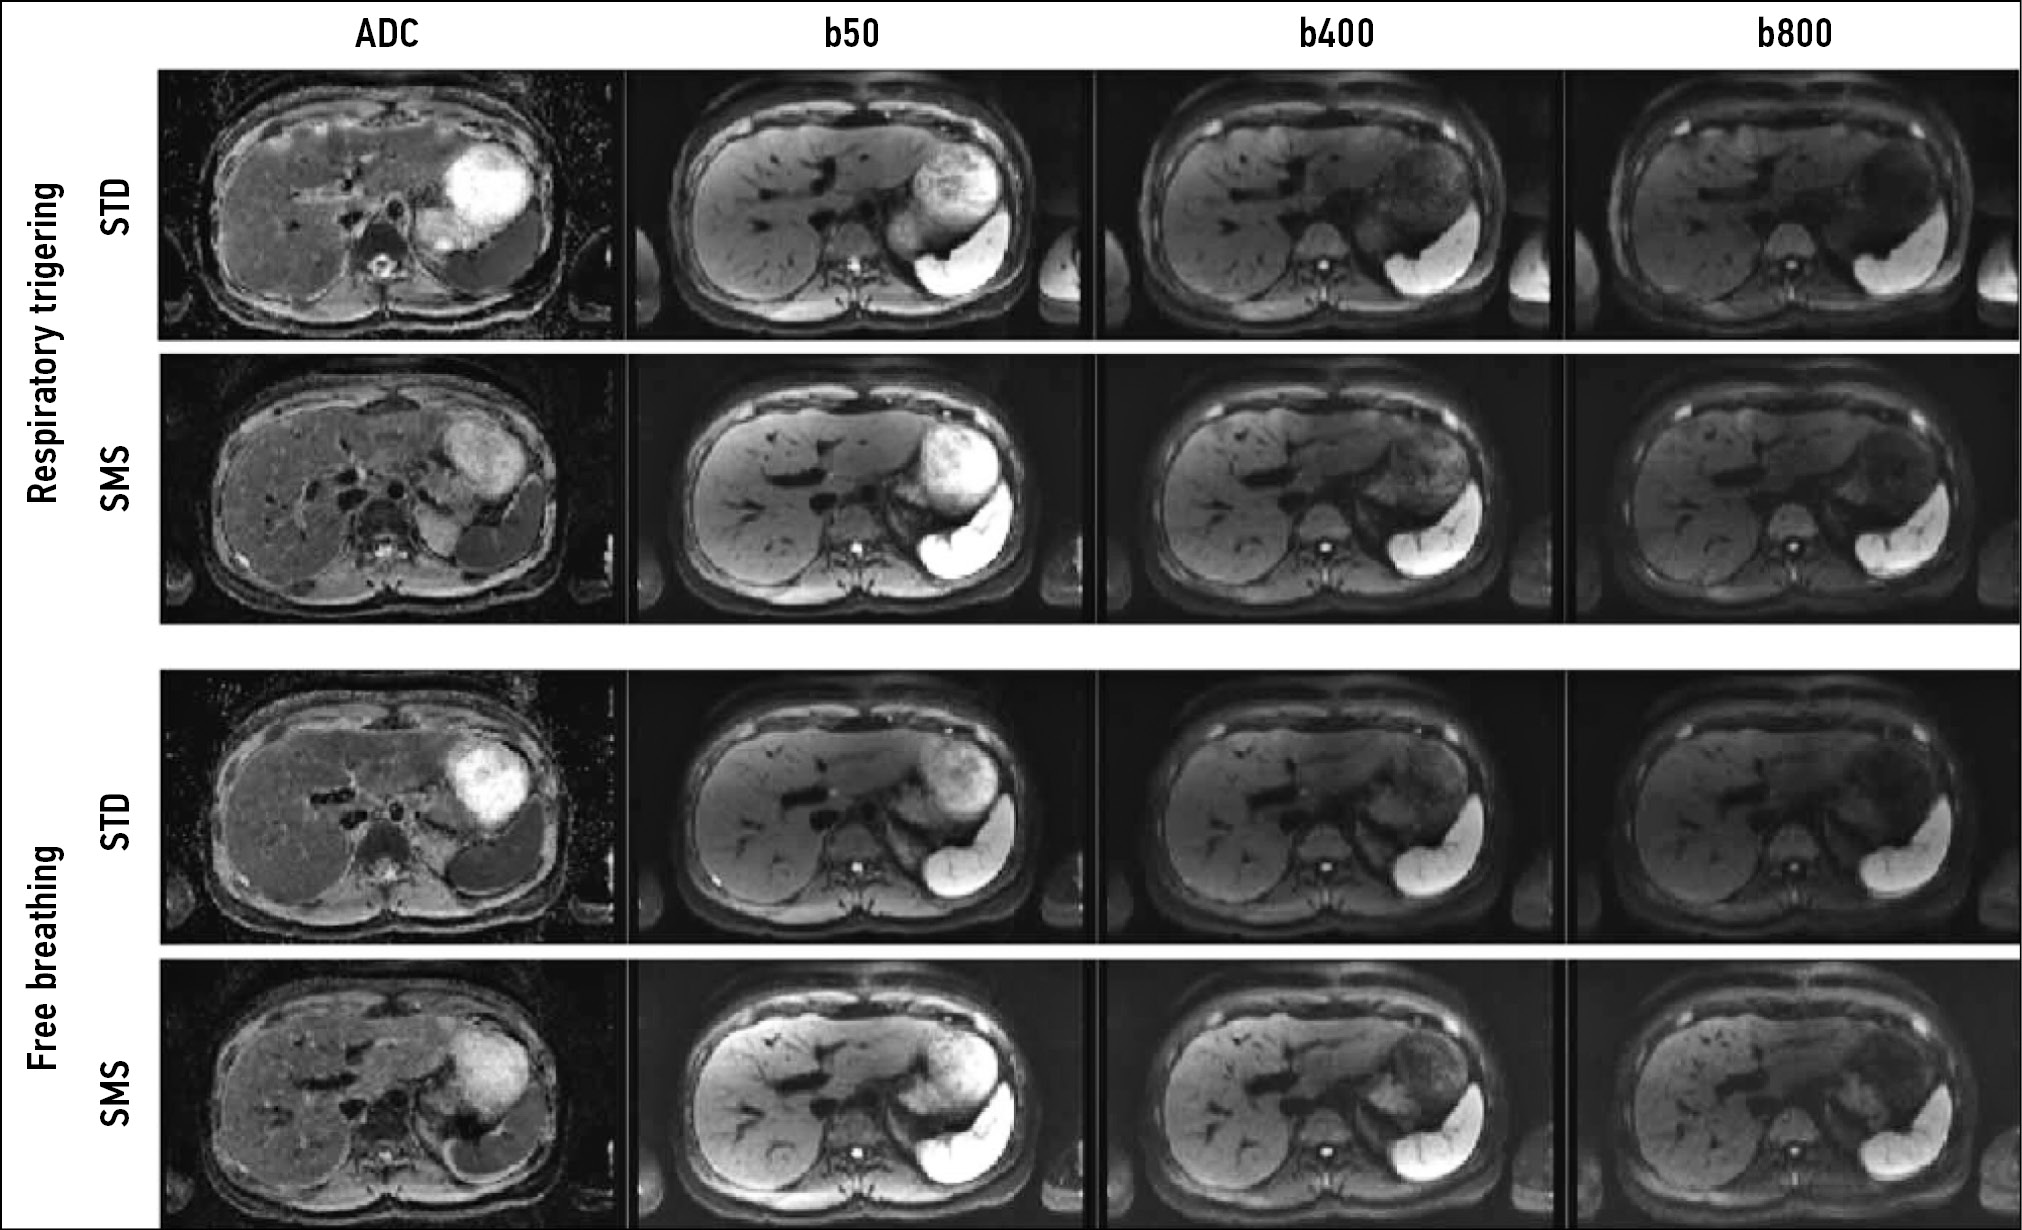

Another important aspect of T1-WIs is the use of intravenous contrast enhancement, including hepatospecific contrast agents. For example, gadoxetic acid has a high affinity for hepatocytes and thus allows for better visualization of liver pathologies (Fig. 1).

Figure 1. Liver magnetic resonance imaging with a hepatospecific contrast agent. A hepatocellular carcinoma nodule (arrows): a T2-weighted image: a hyperintense nodule is visualized; b Т1-weighted image, arterial phase: a ring-like contrast uptake is visualized; c Т1-weighted image, hepatospecific phase, 20 min after contrast agent injection.

Contrast agents shorten the T1 relaxation time, resulting in higher signal intensity on T1-WIs. Depending on the blood supply to focal or diffuse lesions in parenchymal organs, various contrasting patterns are distinguished, which in general differ from those in adjacent unaffected tissues. Arterial phase imaging is accomplished by short sequences immediately after the administration of gadolinium-based contrast agents.